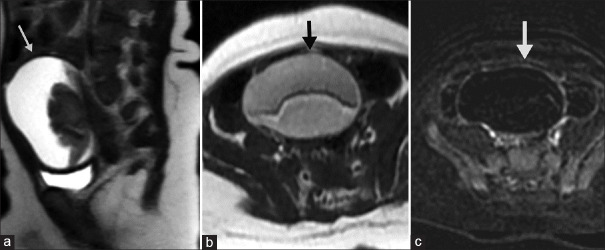

摘要:产前超声波扫描的常规安排导致胎儿卵巢囊肿的检测频率增加。虽然大多数卵巢囊肿会自然消退,但有些囊肿可能会长成大的囊肿,并发生扭转,继而自动切除。然而,产前和产后扫描可能无法发现这种情况。我们报告了一例产前诊断为卵巢囊肿的病例,该囊肿保守治疗无效,且在产后超声检查中不断增大。术前超声波和磁共振成像未能检测到自体囊肿。腹腔镜手术为新生儿和婴儿卵巢囊肿的切除提供了一种安全有效的方法。

Abstract: The routine schedule of antenatal ultrasound scans has led to an increased frequency of detection of foetal ovarian cysts. Although most of them regress spontaneously, some may grow into large cysts and undergo torsion followed by auto-amputation. However, pre- and post-natal scans may fail to identify this event. We report a case of a prenatally diagnosed ovarian cyst that failed to resolve conservatively and was increasing in size in post-natal ultrasounds. Pre-operative ultrasound and magnetic resonance imaging failed to detect the auto-amputation. The diagnosis was confirmed on laparoscopy which offers a safe and effective method for the removal of ovarian cysts in neonates and infants.